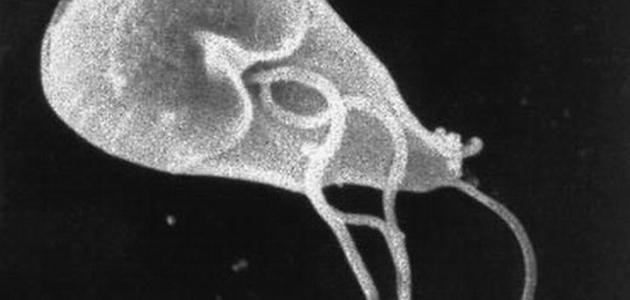

طفيليات الجيارديا

تُعرّف الطفيليّات (بالإنجليزية: Parasites) على أنّها كائنات حية دقيقة تعيش على كائن حيّ آخر، وتُعتبر الجيارديا (بالإنجليزية: Giardia) طفيليّاتٍ مجهرية توجد على سطح التربة، والطعام، والماء الملوّث ببراز الحيوان أو الإنسان المصاب بها، وتمتاز بغلافٍ خارجيٍّ يمكّنها من العيش لفتراتٍ طويلةٍ خارج أجسام الكائنات الحية، وقد تصل هذه الفترات إلى أسابيع أو شهور عديدة، وكذلك فإنّ هذا الغلاف يجعلها مقاومةً للمعقّمات المحتوية على الكلور، وتتسبّب هذه الطفيليات بداءٍ يُعرف بداء الجيارديات (بالإنجليزية: Giardiasis)، وعند إصابة الإنسان أو الحيوان بها فإنّها تعيش في أمعائه وتنتقل إلى برازه، وتجدر الإشارة إلى أنّ هذا النوع من الطفيليّات قد يُوجد في أي منطقة من الولايات المتحدة الأمريكية، وتُقدّر مراكز مكافحة الأمراض واتقائها (بالإنجليزية: Centers for Disease Control and Prevention) أنّ ما يُقارب 16.000 شخص يُصاب بهذه العدوى في أمريكا سنوياً، وكذلك قد تحدث العدوى في أيّ من مناطق العالم وخاصةً في الدول النامية، إذ إنّ ما يُقارب 20-30% من الأشخاص الذين يسكنون هذه المناطق معرّضون للإصابة بعدوى الجيارديا مرة واحدة على الأقل في حياتهم.